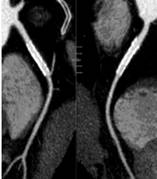

※肝脏、胰腺、肾脏CT-DSA 及灌注功能一站式检查